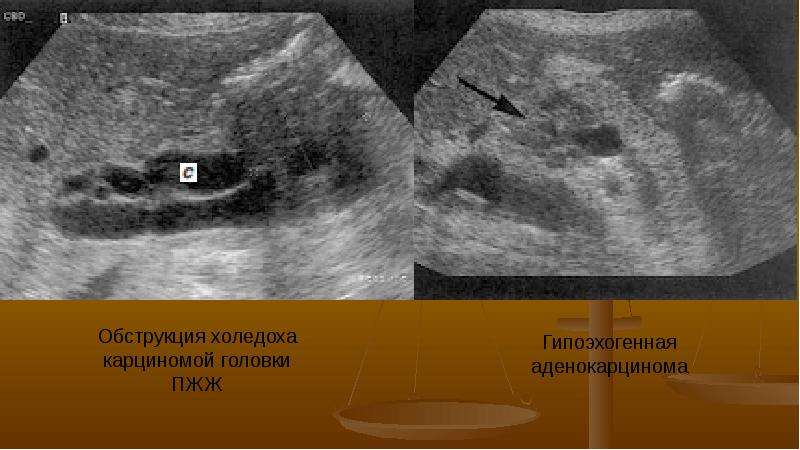

УЗИ диагностика кольцевидной поджелудочной железы: что важно знать